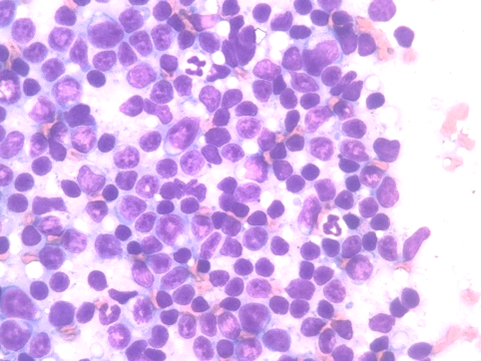

細胞診

細い針で腫瘍の細胞を採取し、染色を行ったあと顕微鏡で細胞の形態を検査します。

病理検査

腫瘍の一部、または全部を切除したものを検査します。